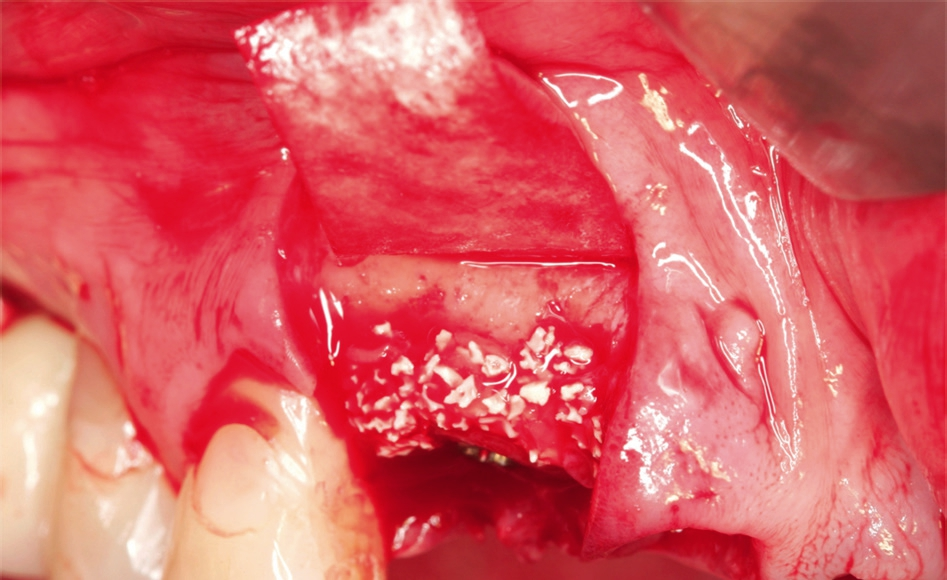

Anschließend wurde das Implantatbett durch den Ring vorbereitet und ein Straumann Bone Level Tapered (BLT) Implantat ø 3,3 mm gesetzt (Abb. 7 und 8). Insgesamt erfolgte die Implantation von zwei maxgraft® bonerings 6 mm und zwei Straumann BLT Implantat ø 3,3 mm 10 mm (Abb. 9). Zur Unterstützung der Weichgewebeheilung wurde platelet-rich fibrin (PRF) aus dem Blut der Patientin gewonnen (Abb. 10). Das PRF wurde sowohl in Verbindung mit dem Knochenersatzmaterial (cerabone®) (Abb. 11), als auch als Membran über der Barrieremembran (Jason® membrane) (Abb. 12) eingesetzt. Zum Erhalt der 1er Schneidezähne wurde eine Socket Preservation mit einem Knochen-Schleimhaut-Transplantat aus der tuber maxillae durchgeführt (Abb. 14 und 15). Explantation erfolgte mithilfe eines 6er Trepans rechts und links aus dem Kieferkamm (Abb. 14).